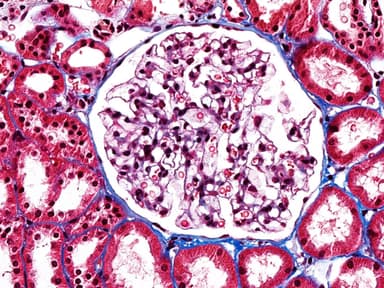

Kidney FSGS

Interpretation of Renal Biopsies

Comprehensive training in renal pathology with focus on glomerular and tubulointerstitial diseases.